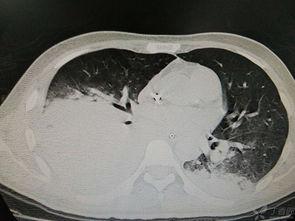

半肝移植的案例

让我们来看一个真实的案例。张先生是一位患有肝硬化患者,他的肝脏功能已经严重受损。经过医生评估,张先生符合进行半肝移植的条件。手术非常成功,张先生的肝脏功能得到了明显改善,生活质量也得到了很大提升。